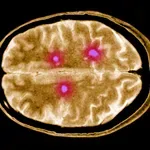

Če opazite, da se nekdo tako vede, takoj k zdravniku: možno je, da ima možganski tumor

Nenavadne, na prvi pogled nenevarne spremembe v vedenju